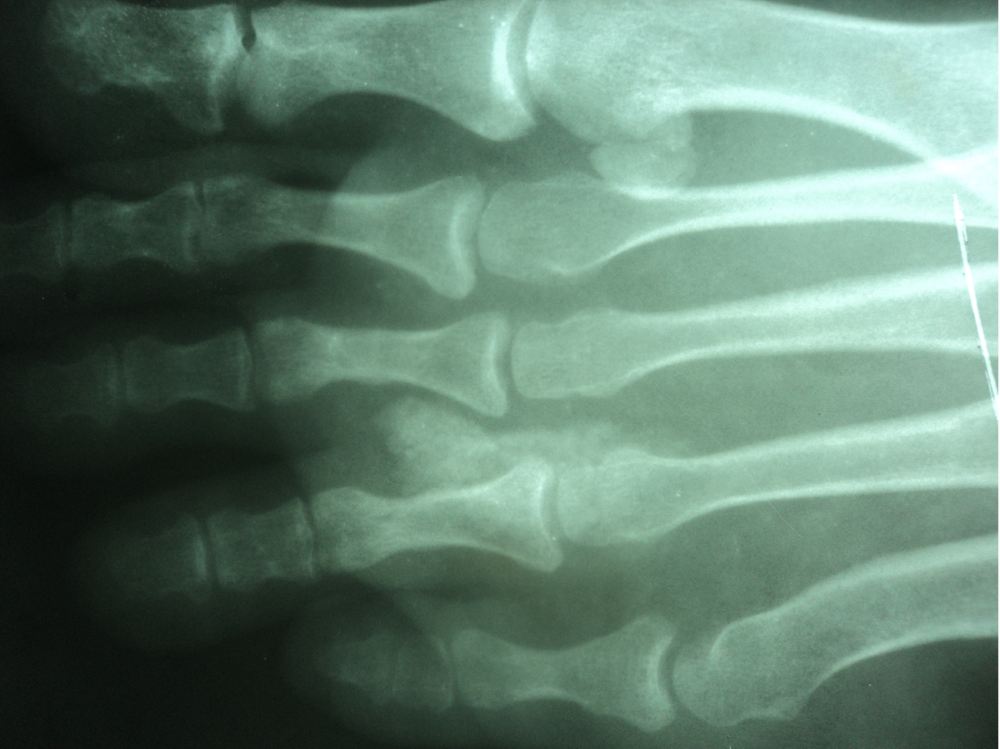

Radiology description

- Plain radiography:

- Joint effusion (earliest sign)

- Subcortical bone cysts, chondrocalcinosis (5%)

- Specific delicate bone erosions due to tophi occur with chronicity

- Punched out erosions with sclerotic margins (rat bite erosions)

- Punched out lytic lesions in bone

- Osteonecrosis

- Olecranon and prepatellar bursitis

- Hyperdense periarticular soft tissue swelling (Eur Radiol 2008;18:621)